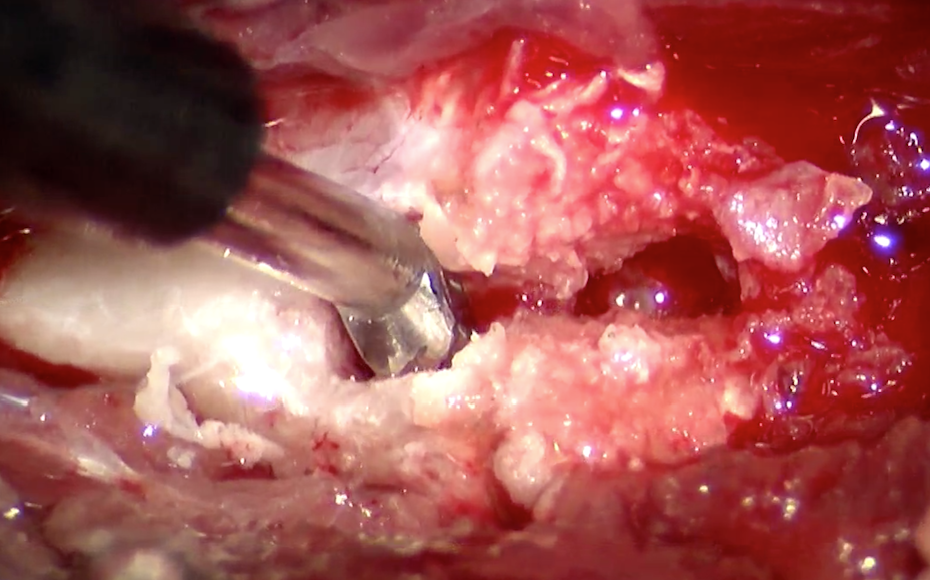

椎間板物質を鉗子で摘出しているところです。

椎間板物質が摘出され、一番奥に神経が見えています。